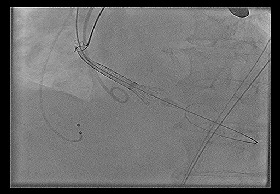

◆2015年1月17日行TAVI术。

◆植入29mm CoreValve人工支架瓣膜一枚。

术后症状明显缓解,近一年未因心衰住院;

一年期复查心超,未见主动脉瓣狭窄和关闭不全。